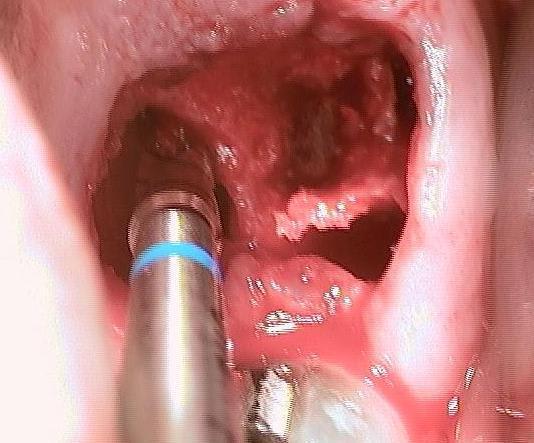

Un patient de 52 ans présente une fracture de racine au site 26.Après division de la racine, extraction de la dent,préparation de la cavité avec un foret conique triangulaire (3 faces,condensation de l´os), puis implantation à 50 Ncm (implant 10mm long, 4,5mm diamètre).Utilisation d´acide hyaluronique pour stimuler la synthèse des ostéoblastes.Pose d´un clip gingival pour préformer la gencive.Après 7 semaines, réalisation d´une empreinte fermée en 5 minutes.Une semaine après, fixation de la couronne définitive ( on observe déjà une ostéointégration).

Pour laisser entrevoir la technique MIMI (Minimale Invasive Method Implantation) développée par le Dr Armin Nedjat voilà la séquence en photos et radios d'un cas d'extraction implantation immédiate technique simplifiée.